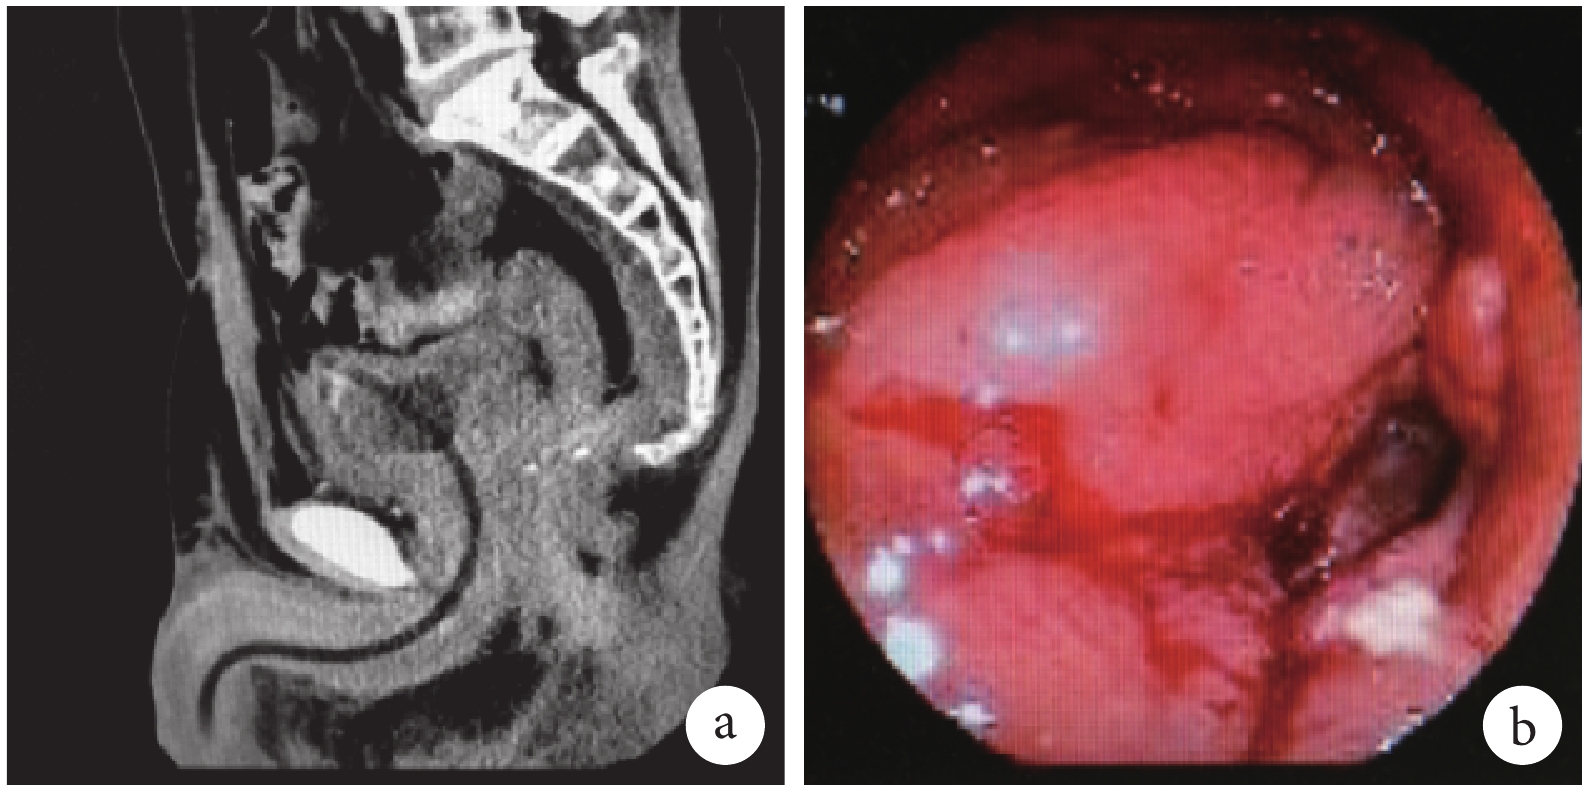

病例 1,曾行新輔助放療,術中盆腔與右側輸尿管粘連致密,分離困難。術后肛門溢出液檢查結果顯示肌酐水平明顯升高,達 2 800 μmol/L;CT 檢查提示殘余直腸腸壁增厚及盆腔軟組織病變,腫瘤復發可能性大,盆腔多發臟器受侵犯及粘連,直腸殘端瘺,骶前軟組織增厚(圖 1);泌尿系 CT 尿路造影提示右腎積水,右側輸尿管下段未見造影劑填充。綜合考慮術中可能存在右側輸尿管損傷,術后直腸殘端愈合不良,合并腫瘤復發,形成右側輸尿管直腸殘端瘺。

病例 2,為接受新輔助放療直腸癌患者,小腸造瘺還納后逐漸出現尿路感染,術后 1、9 及 12 個月復查 CT 時均可見直腸吻合口腸管管壁增厚,周圍脂肪間隙模糊,與精囊腺分界不清(圖 2a)。PET-CT 提示直腸吻合口周圍腸瘺合并感染可能。消化道造影提示直腸吻合口瘺,逆行尿路造影見尿道顯影不全、狹窄。腸鏡檢查提示距離肛門 5 cm 吻合口旁袋狀盲端多發息肉樣隆起伴竇道形成(圖 2b)。考慮該患者 Dixon 術后出現慢性放射性腸炎導致吻合口愈合不佳,形成慢性直腸尿道瘺,小腸還納后出現癥狀。